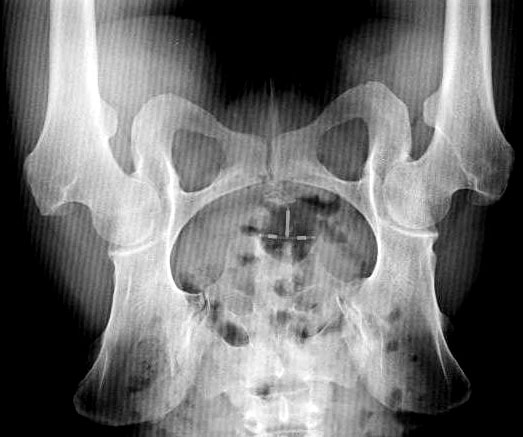

radiografia (backlight)

60x60x7cm